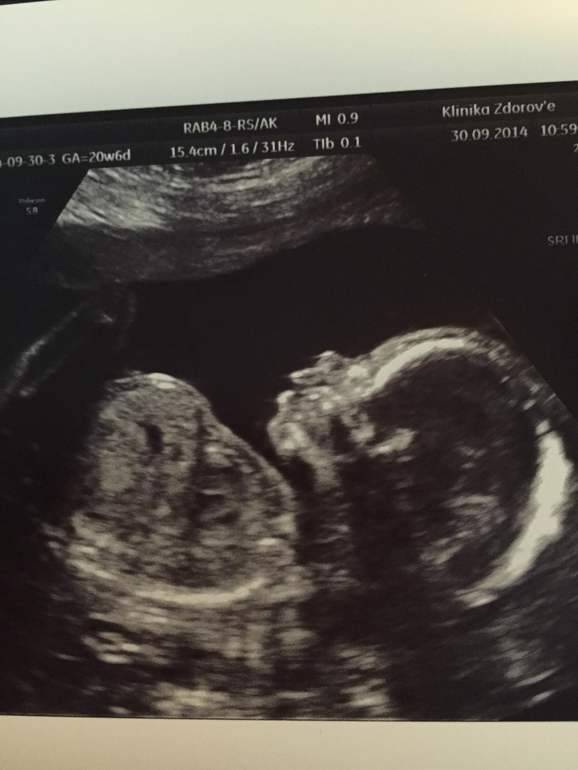

Была на УЗИ в 20-21 неделю, мой кроха показал язык!) так было смешно, как он скривил мордашку, высунул язык и тут же убрал его обратно..заснять, конечно, не успели...

Вот наше фото